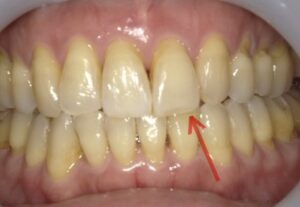

【症例2】50代・矯正は難しいと言われ半ば諦めていたガタガタの改善

「数カ所の歯科医院で相談をしたが、矯正が難しいと言われ諦めかけていた」という50代女性のケースです。前歯が元々欠損しているため真ん中を合わせることはできませんが、ガタガタはIPRや側方拡大を行い治すことができました。

仕上げに前歯のすり減りをダイレクトボンディングで直し、より整った印象にしています。

- 治療方法: ワイヤー矯正上下

- 治療期間: 12ヶ月

- 治療費用: 77万円(税込)

- 治療のリスク・デメリット:ブラックトライアングル

- ポイント: 比較的短期間のプランで、前歯の見た目と清掃性を大幅に向上させました。